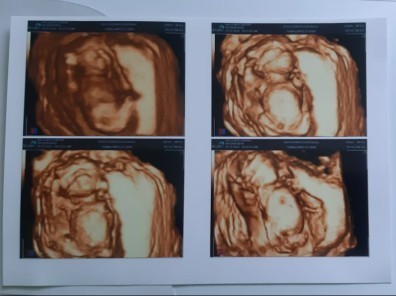

Ini bunda foto usg baby aku

tangannya nutupin mulut huhu

USG 4d di usia 24minggu,,

ini waktu Uk 33 w bun😅

32weeks baby girl.. 💗